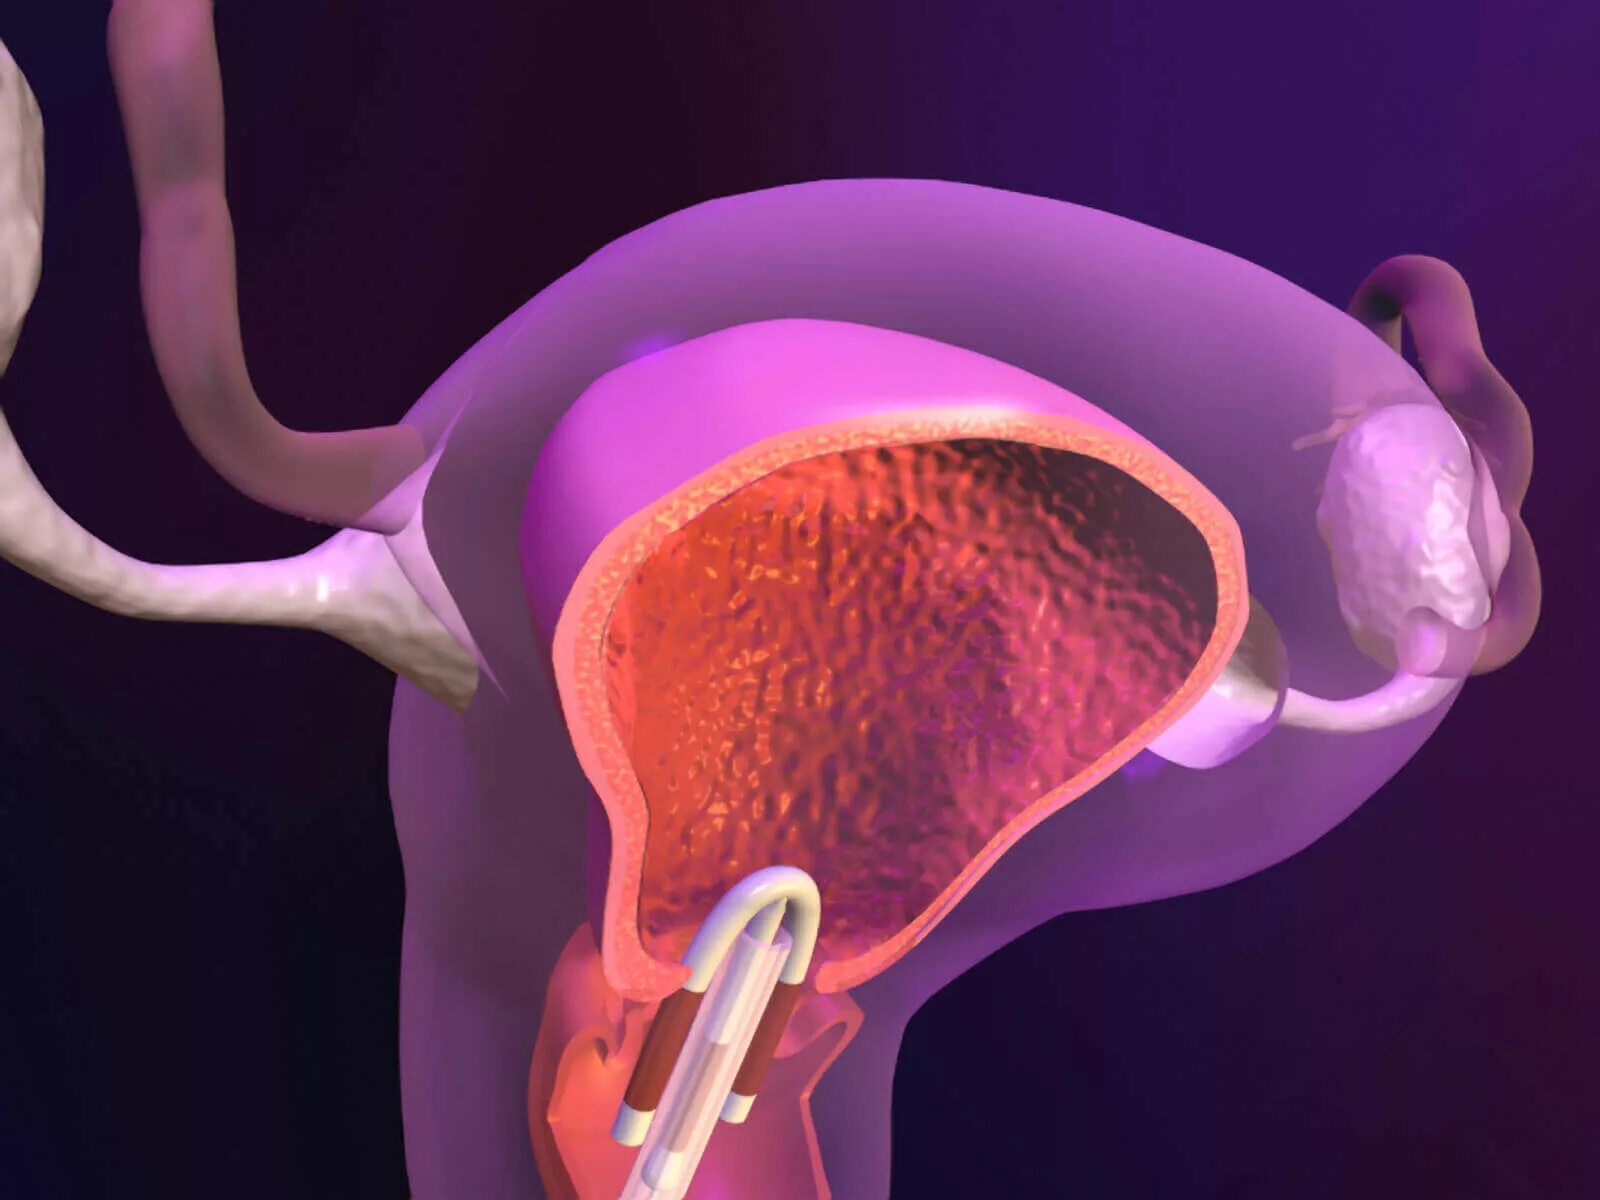

Вмс шейки матки